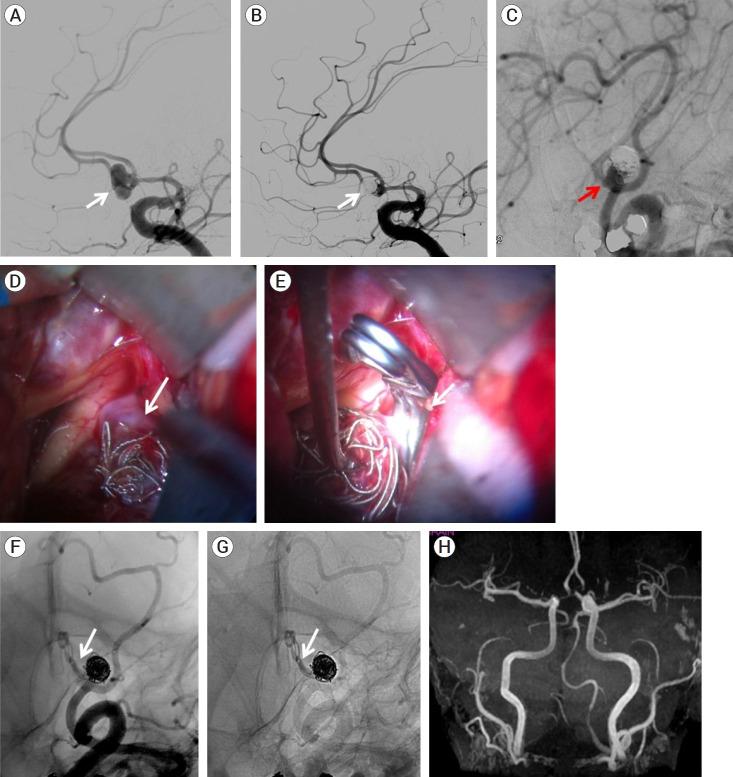

Retrospective analysis of nine (9) patients' data and final clinical/angiographic outcomes, who underwent surgical clipping of IAs in our center following initial endovascular treatment, over a 12-year period (2010-2022). Regarding the literature review, data were extracted from 48 studies including 969 patients with 976 aneurysms.

9 patients (5 males - 4 females) were included in the study with a mean age of 49 years. Subarachnoid hemorrhage was the initial presentation in 78% of patients. Aneurysms' most common location was the middle cerebral artery bifurcation (5/9) followed by the anterior communicating artery (3/9) and the internal carotid artery bifurcation (1/9). Indications for surgery were coil loosening, coil compaction, sac regrowth, and residual neck. Procedure-related morbidity and mortality were zero whereas complete aneurysm occlusion was achieved after surgical clipping in all cases (100%). All patients had minimal symptoms or were asymptomatic (mRS 0-1) at the final follow-up.

9例患者(5例男性 - 4例女性)纳入研究,平均年龄为49岁。78%的患者最初表现为蛛网膜下腔出血。动脉瘤最常见的位置是大脑中动脉分叉处(5/9),其次是前交通动脉(3/9)和颈内动脉分叉处(1/9)。手术指征为弹簧圈松动、弹簧圈压缩、瘤囊再生长和残余瘤颈。与手术相关的发病率和死亡率为零,所有病例(100%)在手术夹闭后均实现了动脉瘤完全闭塞。所有患者在最后一次随访时症状轻微或无症状(改良Rankin量表评分0 - 1分)。